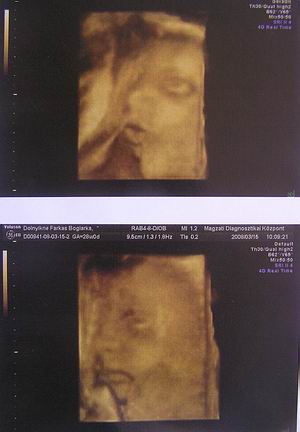

Ma voltunk 4D-sen, minden oké a KISCSAJJAL!, ami mostmár tuti (jöhetnek a rózsaszín csodák minden mennyiségben ;))

Teszek fel pár képet: olyan édi és már 1036 gramm!

Kép Kép

Az első képen nagyon tisztán látszik a pofija és naon cuki!!!

Ahogy bari is írta,hihetetlen,hogymár 1 kiló felett vannak!

Bogi nagyon szép a abád,de a kép minőség nem annyira jó

Szerintem is írtó cukor. Ásítozott, szopizta az ujját, még a nyelvecskéjét is kidugta nekünk. Az UH végére pedig elaludt. :lol: